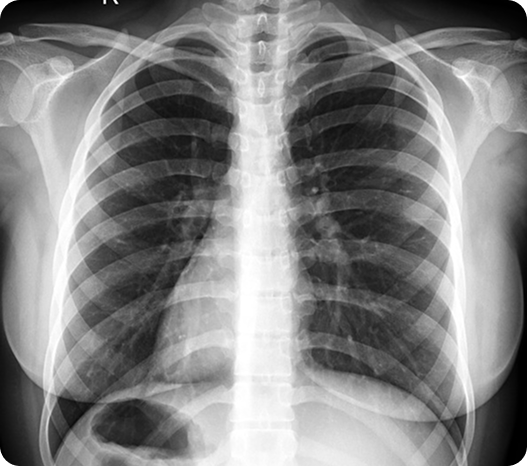

Situs Inversus is a rare congenital condition in which a person’s internal organs are mirrored from their normal positions. For example, the heart may be located on the right side of the chest instead of the left — a condition called situs inversus totalis when all major organs are affected.

Situs Inversus is a rare condition where a person’s internal organs are arranged as a mirror image of the typical layout. For example, the heart may be on the right side of the chest instead of the left. It’s usually present from birth and affects less than 1 in 10,000 people.

Situs Inversus is often discovered during imaging tests like X-rays, ultrasounds, or CT scans — sometimes by accident. In newborns, it may be identified shortly after birth if doctors notice unusual heart sounds or other signs.